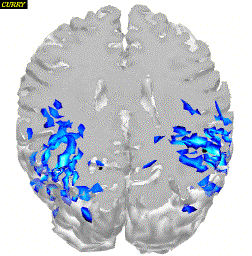

Figure 14. a) Results

of fMRI-constrained MNLS current density reconstruction

(SNR = 15, clipped) and simulated source locations

(black); b) Results of unconstrained MNLS current density

reconstruction (SNR = 15, clipped) and simulated

source locations (black); c) Scale.

7.2 Current Density Results

In the fMRI-constrained Minimum Norm Least Squares (MNLS)

current density solutions, all source locations were retrieved

when using a weight factor of 1.4, even in the case of a

source without corresponding hotspot. However, the time

courses of sources 1 and 2 interfere. Results are shown

in Figure 14 a). For comparison, the results of an

unconstrained solution with WfMRI = 1

are shown in Figure 14 b).